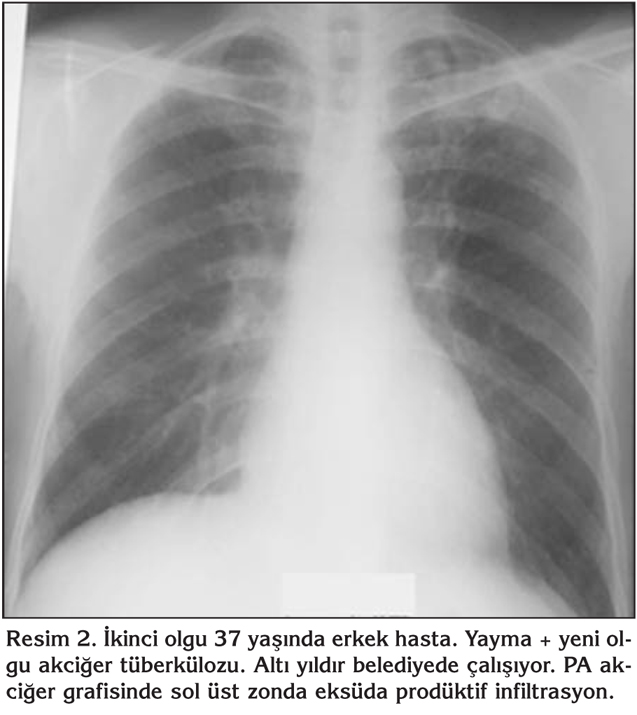

Akci?er t?berk?lozu ??phesi olan 12 olgu incelendi?inde; iki olgu yayma pozitif yeni olgu akci?er t?berk?lozuydu. Bunlardan birinci olgunun mikrografisinde sol akci?er ?st zonda eks?da prod?ktif lezyon, ikinci olgunun ise sa? akci?er hiler b?lgeden perifere uzanan zonda eksuda prod?ktif infiltrasyan mevcuttu (Resim 1,2). Her iki olgu da b?lgede ikamet ediyordu, g?? etmemi?lerdi. Aralar?nda akrabal?k yoktu. Bir olgu 6 y?l, di?er 21 y?ld?r ?of?r olarak ?al???yordu. Be? olgunun daha ?nce t?berk?loz tedavisi ald??? ve tedaviyi tamamlad??? (4 olgu akci?er, 1 olgu plevra t?berk?lozu) tespit edildi. Di?erleri; bir olgu akci?er kanseriydi ve tan?dan bir y?l sonra vefat etti. ?ki olgu pn?moni, bir olguda akci?erde patoloji saptanmad?, di?er olguda meniskus operasyonundan sonra akci?er embolisi geli?ti?i ??renildi (Tablo 2).